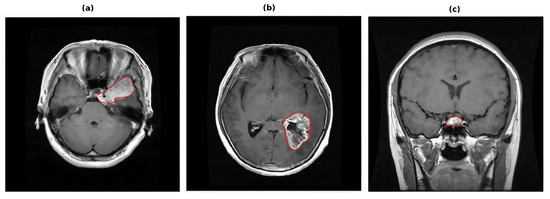

Efficient Uncertainty-Aware Dual-Attention Network for Brain Tumor Detection

by Sitara Afzal and Jong Ha Lee

Mathematics 2026, 14(9), 1421; https://doi.org/10.3390/math14091421 - 23 Apr 2026

Brain tumor detection from magnetic resonance imaging (MRI) is fundamental to computer-aided diagnosis, yet automated models must remain robust to heterogeneous imaging conditions. Despite strong recent progress, many deep learning and transformer-based approaches primarily optimize performance accuracy without explicitly improving feature selectivity and [...] Read more.

Brain tumor detection from magnetic resonance imaging (MRI) is fundamental to computer-aided diagnosis, yet automated models must remain robust to heterogeneous imaging conditions. Despite strong recent progress, many deep learning and transformer-based approaches primarily optimize performance accuracy without explicitly improving feature selectivity and spatial localization, and they typically produce deterministic output without uncertainty estimates, which limits reliability. To overcome these limitations, we introduce UA-EffNet-DA, an uncertainty-aware EfficientNet framework that addresses these limitations through three complementary components. First, EfficientNet-B4 serves as an efficient backbone for discriminative feature extraction. Second, lightweight dual attention modules, comprising channel and spatial attention in parallel, are applied to the model to emphasize what and where discriminative features to focus within MRI slices. Third, Monte Carlo dropout is employed during inference to quantify predictive uncertainty and enable confidence-aware decision. Experiments on two public benchmarks demonstrate strong performance, yielding accuracies of 98.73% on the Figshare dataset and 99.23% on the Kaggle dataset. In addition, explainable AI analysis using Gradient-weighted Class Activation Mapping (Grad-CAM) further indicates that the proposed model concentrates on diagnostically relevant tumor regions rather than background structures, supporting transparent decision-making. Ablation studies confirm the complementary contribution of dual attention refinement and uncertainty-aware inference. Overall, the proposed UA-EffNet-DA framework offers an efficient and interpretable approach for brain tumor detection that supports more reliable clinical decision support through uncertainty-aware predictions. Full article